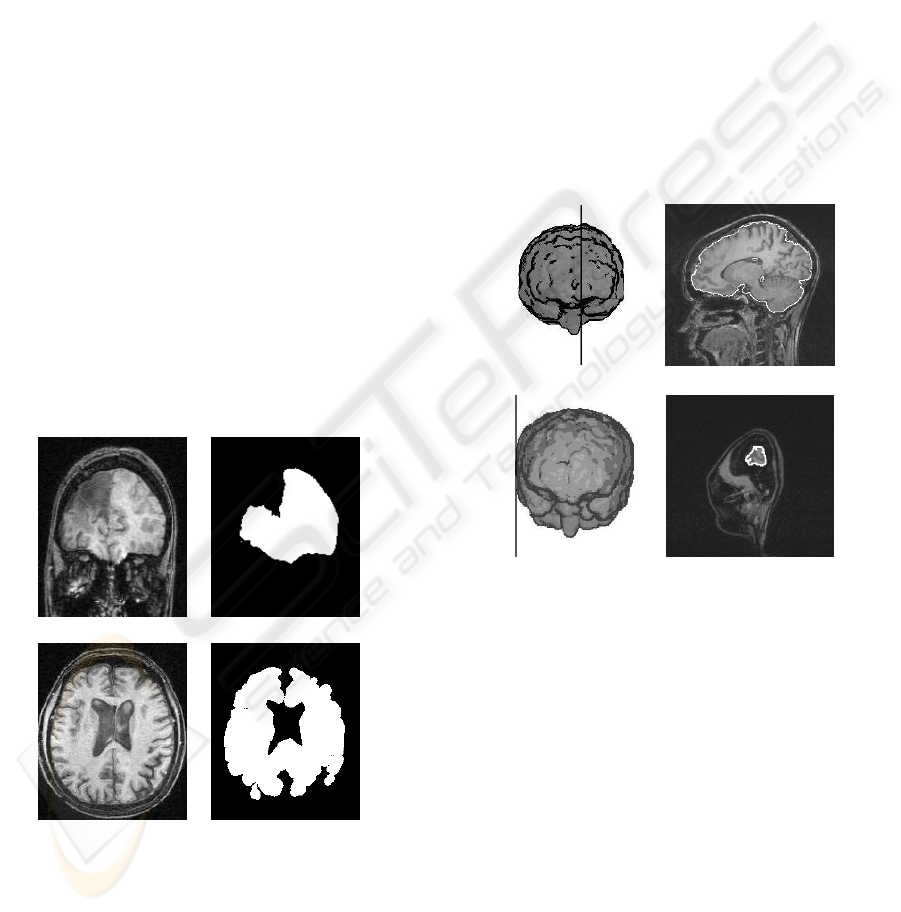

FAST AND ROBUST MID-SAGITTAL PLANE LOCATION IN 3D MR IMAGES OF THE BRAIN